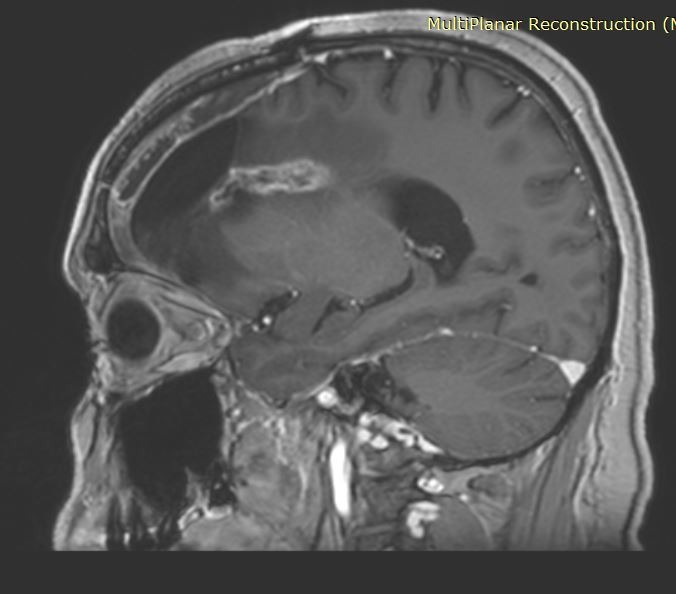

Ασθενής με ιστορικό χειρουργηθέντος γλοιοβλαστώματος παρουσίασε, στις μαγνητικές τομογραφίες παρακολούθησης, την εμφάνιση μιας νέας βλάβης ύποπτης για υποτροπή, η οποία παρουσίαζε σταδιακή αύξηση μεγέθους.

Η βλάβη εντοπιζόταν εν τω βάθει, δηλαδή σε σχετικά βαθιά περιοχή του εγκεφάλου. Με τον ασθενή συζητήθηκαν αναλυτικά οι διαθέσιμες θεραπευτικές επιλογές: είτε νέα κρανιοτομία με αφαίρεση της βλάβης είτε εξάχνωση (καταστροφή) της νέας εστίας με τη χρήση λέιζερ.

Η εξάχνωση με λέιζερ αποτελεί μια ελάχιστα επεμβατική τεχνική, κατά την οποία τοποθετείται ένας λεπτός καθετήρας εντός του όγκου και, με τη βοήθεια ελεγχόμενης θερμότητας, ο όγκος καταστρέφεται. Σε σύγκριση με την ανοιχτή χειρουργική επέμβαση, πρόκειται για μια σαφώς πιο ασφαλή μέθοδο, με σημαντικά ταχύτερη ανάρρωση για τον ασθενή. Επιπλέον, η τεχνική αυτή επιτρέπει τη λήψη ιστού για βιοψία πριν από την καταστροφή του όγκου, γεγονός ιδιαίτερα σημαντικό για τη σωστή διάγνωση και περαιτέρω αντιμετώπιση.

Επίσης, συχνά οι υποτροπές είναι σε σημεία του εγκεφάλου που είναι βαθιά και οι ασθενείς είναι ήδη επιβαρυμένοι από τις ως τώρα θεραπείες.

Το πλεονέκτημα του λέιζερ, πέραν του ότι είναι πολύ λιγότερο επιβαρυντικό για τον ασθενή, είναι ότι η επέμβαση ουσιαστικά πραγματοποιείται στον μαγνητικό τομογράφο και έχουμε τη δυνατότητα να παρακολουθούμε το αποτέλεσμα σε πραγματικό χρόνο (real time).

Στην προκειμένη περίπτωση η βλάβη καταστράφηκε πλήρως.